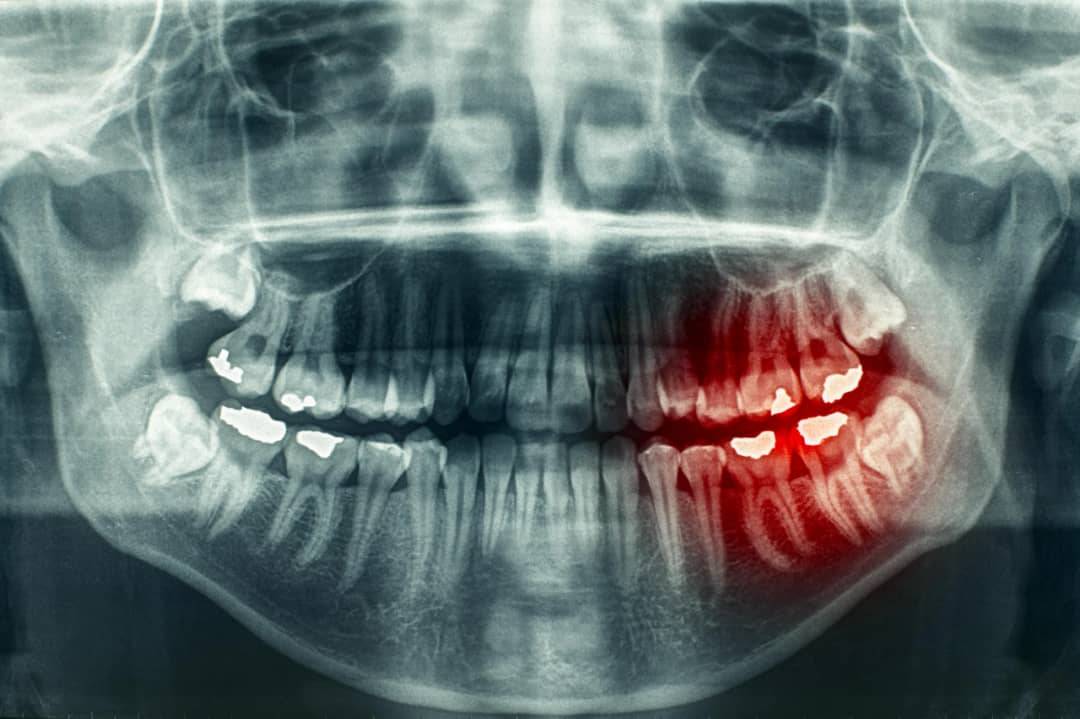

رادیوگرافی دندان در موارد زیادی کاربرد دارد و با کمک آن میتوان مشکلات دندان را بررسی کرد. میتوان گفت که بدون رادیوگرافی یا عکسبرداری از دندان یک دندانپزشک نمیتواند شدت و موقعیت دقیق پوسیدگی دندان را تشخیص دهد. از کاربردهای دیگر آن میتوان به موارد زیر اشاره کرد :

- تشخیص مشکلاتی مانند کیست، تومور و آبسه

- تشخیص مشکلات دهانی مانند پوسیدگی دندان، ساختارهای دندانی پنهان ( مانند دندان عقل ) و غیره

- تشخیص و بررسی رویش دندان های اضافه، غایب، جابه جا شده و یا دندان هایی که به درستی در لثه رویش نیافته اند

تصمیم گیری در مورد زمان و نوع رادیوگرافی بر عهده دندانپزشک می باشد. این تصمیم گیری پس از معاینه کلینیکی دهان بیمار و بسته به شرایط او و ناحیه مورد نیاز به رادیوگرافی انجام می شود. یکی از دلایلی که ممکن است دندانپزشک به شما پیشنهاد انجام رادیوگرافی از دندان را بدهد، تشخیص پوسیدگیهای اولیه بین دندانهاست که احتمال دارد در معاینات کلینیکی از دید دندانپزشک پنهان باشد. در برخی مواقع، ظاهر دندان سالم به نظر میرسد، ولی دندانپزشک با استفاده از رادیوگرافی میتواند پوسیدگیها را تشخیص دهد. همچنین تشخیص وضعیت استخوان نگهدارنده دندان، ریشه و دندانهای نهفته از مواردی است که نیاز به تهیه رادیوگرافی از دندان دارند.